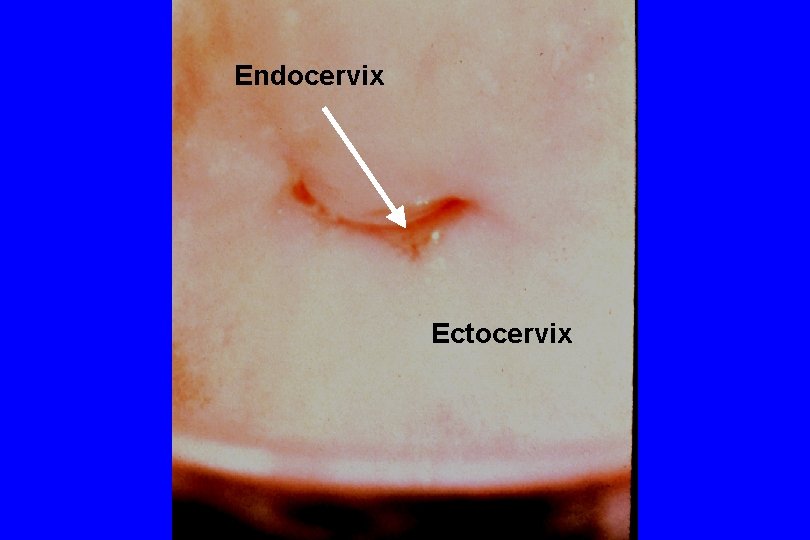

Endocervix Ectocervix